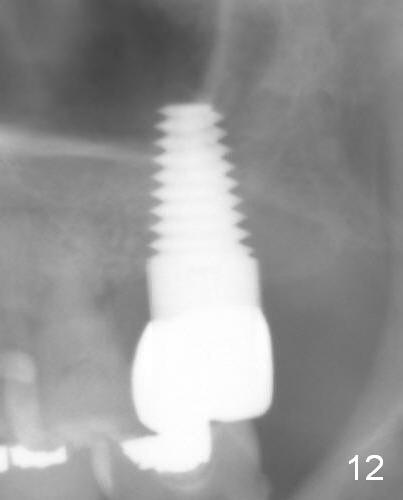

Panoramic X-ray is taken 6 months post cementation (Fig.12). The distobuccal defect seems to persist.